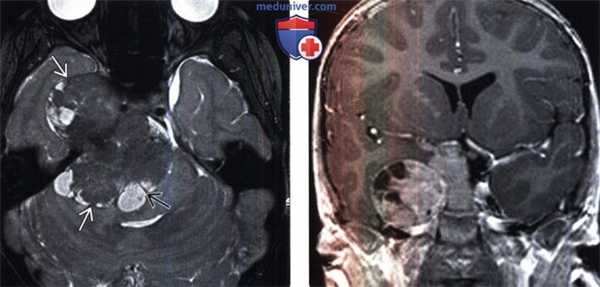

(Слева) Злокачественная менингиома, инфильтрирующая кожу волосистой части головы, череп и смежные отделы головного мозга. Протяженной вазогенный отек изображен серым цветом. Обратите внимание на остеолизис, инвазию твердой/паутинной мозговой оболочки, «грибовидную» форму опухоли и ее «вплетение» в головной мозг.

(Справа) МРТ, постконтрастное Т1 -ВИ, сагиттальный срез: злокачественная менингиома, накапливающая контрастное вещество, и вовлекающая в процесс кожу головы, череп и смежные отделы головного мозга. Обратите внимание на «грибовидное» прорастание опухоли через твердую мозговую оболочку, выраженный гипоинтенсивный отек мозговой ткани. (Слева) МРТ, Т2-ВИ, аксиальный срез: у мужчины 71 года визуализируется объемное образование с четкими контурами, прилежащее широким основанием к твердой мозговой оболочке по ходу большого крыла клиновидной кости. Объемное образование изоинтенсивно по отношению к коре, отчетливо визуализируется ликворная щель, признаков локальной инвазии мозгвой ткани не отмечается.

(Справа) МРТ, постконтрастное Т1-ВИ, режим подавления сигнала от жира, аксиальный срез: интенсивное равномерное контрастное усиление. При операции признаков инвазии смежной мозговой паренхимы выявлено не было. При патоморфологическом исследовании была диагностирована менингиома grade II.